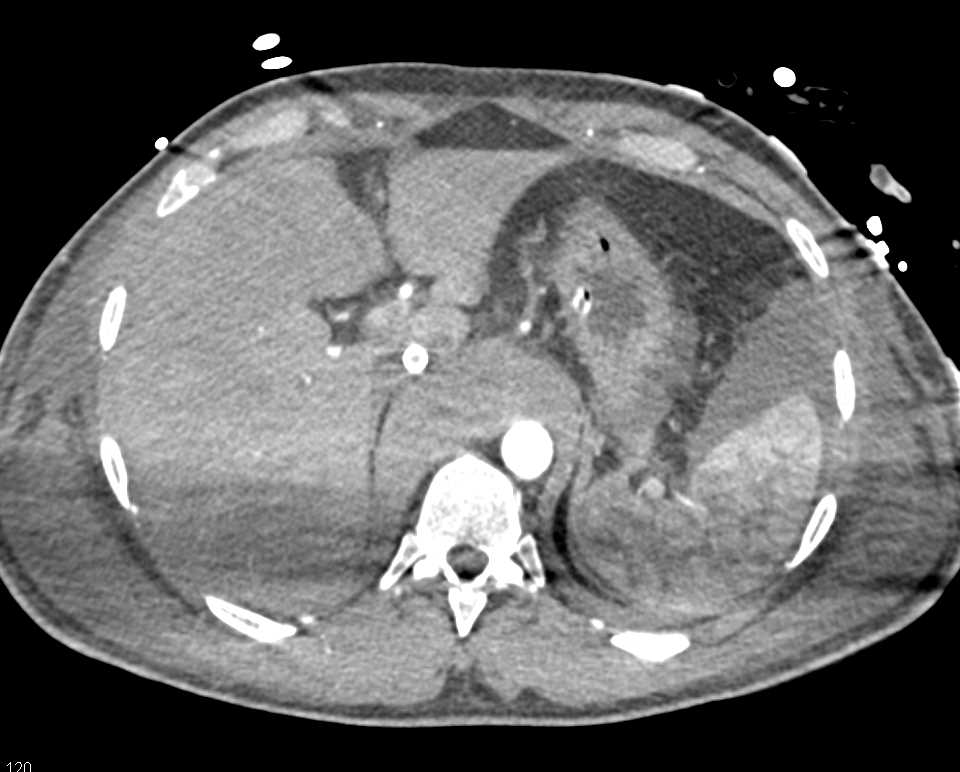

Pneumoperitoneum due to Perforated Rectum